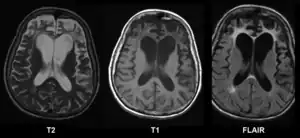

| Brain MRI of a 65-year-old female person with frontotemporal dementia. Cortical and white matter atrophy of the frontal lobes is clear in all images. | |